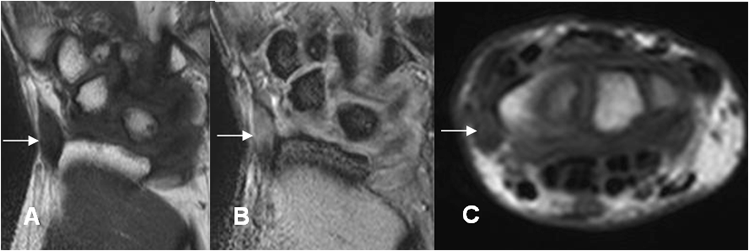

Fig 94 B. Tenosinovitis de Quervain.

A: RM coronal en T1, B: RM coronal en GE y C: RM axial en T1. Tendón del abductor largo del pulgar engrosado y con alteración de su señal, por tendinitis crónica.